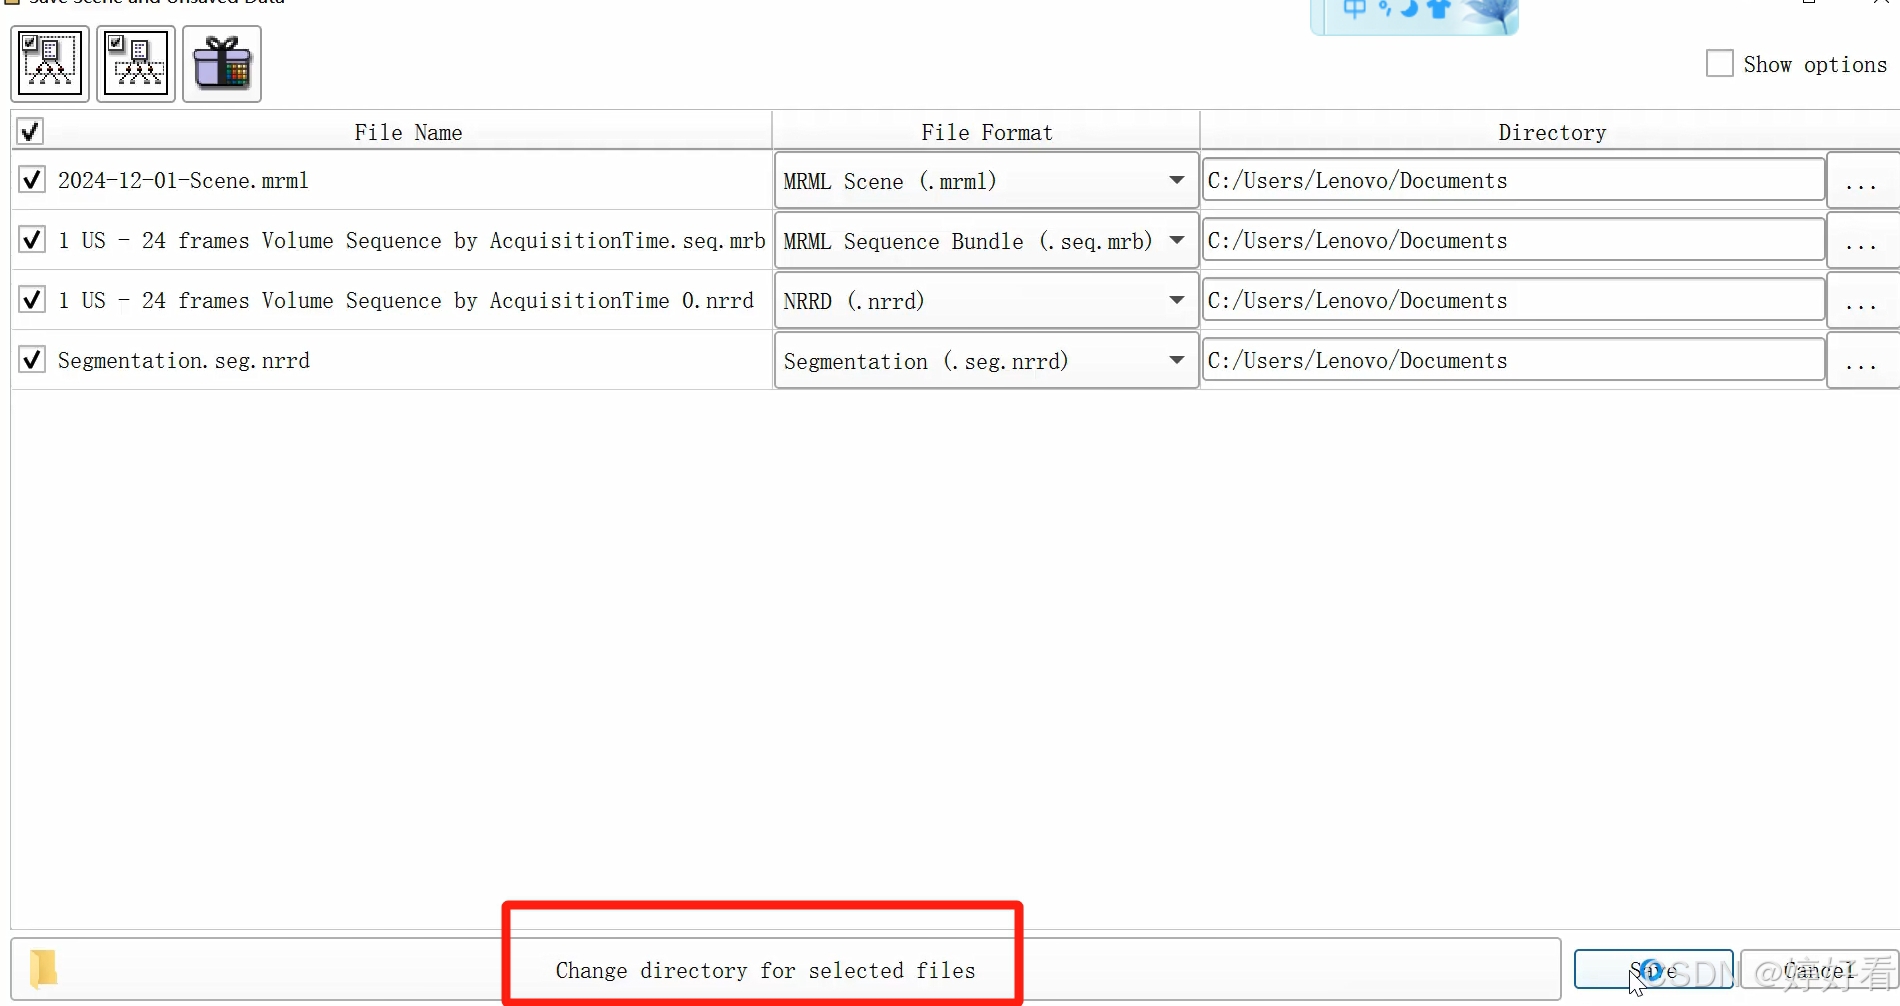

也可以同时修改4个文件的保存路径。

最后,选择保存。